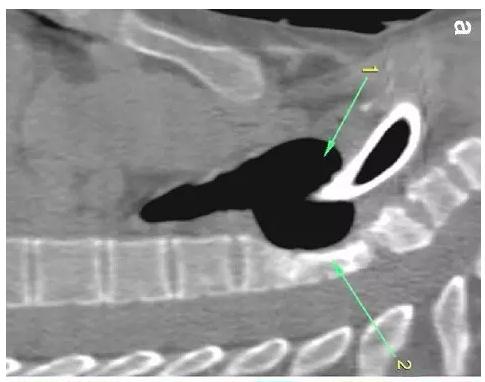

胸部CT顯示氣切套管氣囊周?chē)鷼夤軘U(kuò)張,胸1-4椎體前部受到侵蝕(下圖a-c)。

下圖箭頭1為氣切套管氣囊緊貼T1-4椎體水平,造成椎體前部受到侵蝕(箭頭2):